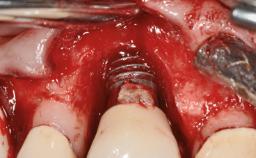

A 77-year-old male patient was referred for the management of frequent and repeated acrylic fracture of his existing mandibular fixed full-arch implant-supported metal/acrylic prosthesis. He also complained about softtissue soreness and the lack of retention and stability of his maxillary removable partial metal/acrylic prosthesis. Both prostheses had been delivered two years previously as part of his full-mouth rehabilitation (caries, tooth wear, tooth fracture). His medical history revealed high blood pressure, controlled with the use of antihypertensive medication.

# of Implants 5

Type of Implants Two-Piece

Defining Characteristics Fully edentulous lower jaw to be rehabilitated with two or more implants

Modality > 4 implants, extending to mental nerve region